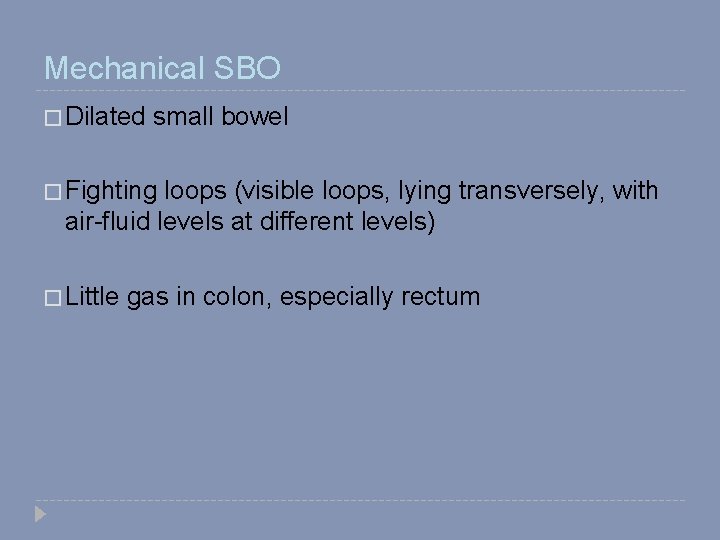

Mechanical SBO � Dilated small bowel � Fighting loops (visible loops, lying transversely, with air-fluid levels at different levels) � Little gas in colon, especially rectum